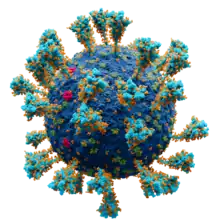

- ... vinca alkaloids are chemotherapy drugs that inhibit the polymerization of tubulin, whereas taxanes are produced by plants of the genus Taxus that inhibit tubulin depolymerization?